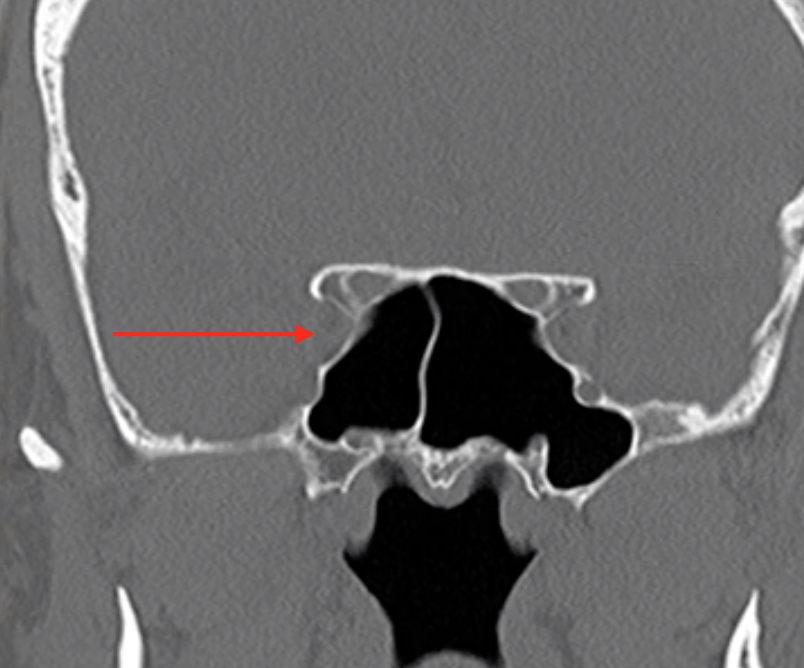

Superior Orbital Fissure

• Structures passing through here:

• CN 3, 4, 5-V1, 6

• Superior ophthalmic vein